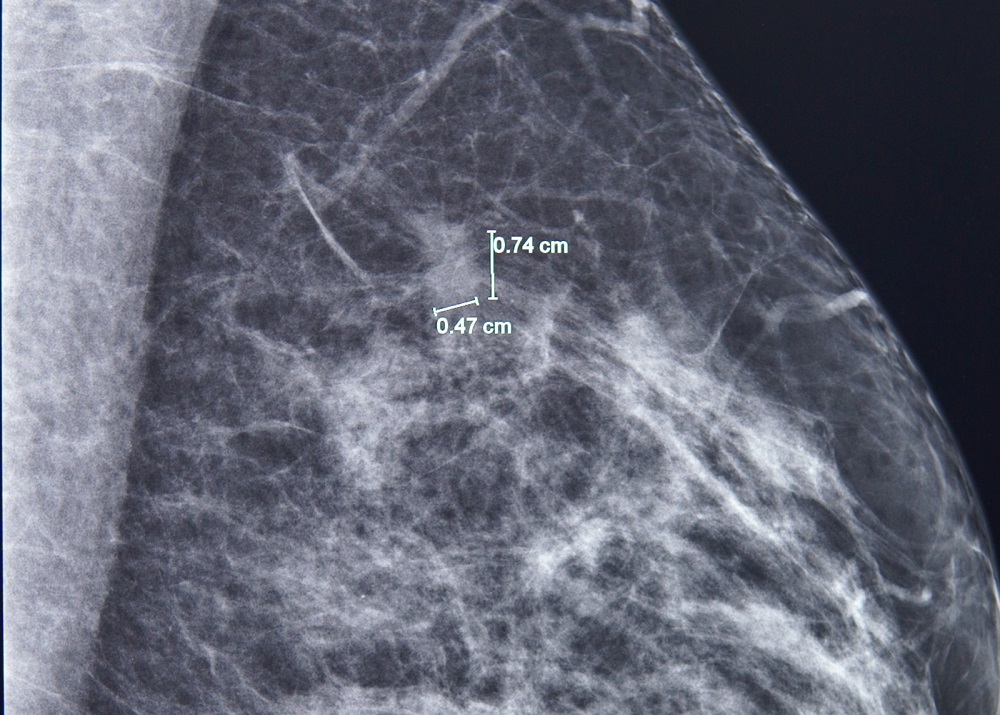

Kết quả nhũ ảnh tìm ra một tổn thương nhỏ, khoảng 7mm ở vú trái. BS.CKI Phùng Ngọc Thư - Trưởng Trung tâm Chăm sóc tuyến vú FV cho bệnh nhân chụp thêm cộng hưởng từ (MRI) do mô vú của bà A. khá đặc. Qua phim chụp MRI, bác sĩ Thư phát hiện thêm một nốt tổn thương khác, chỉ 3mm.

Phát hiện tổn thương 7mm ở vú trái bằng chụp nhũ ảnh - Ảnh: FV